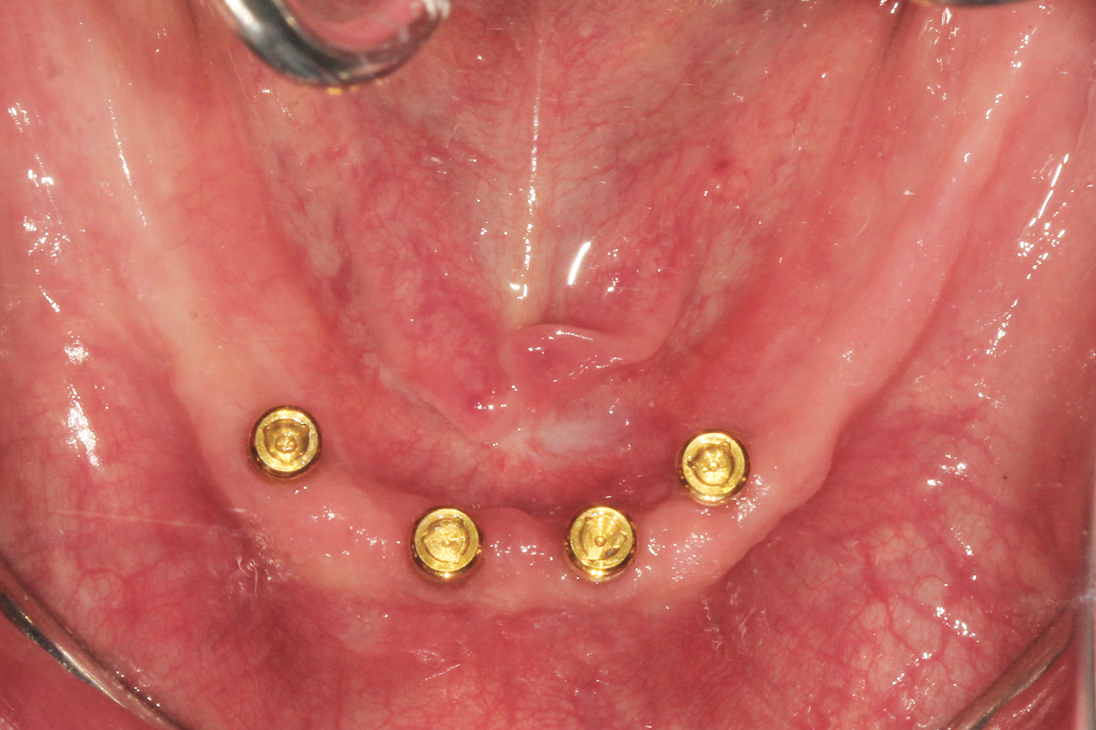

A patient was referred to the practice by another clinician for the fabrication of a functional, stable prosthesis. He presented with four existing implants in the anterior mandible that were fitted with stud-style attachments (LOCATOR®, Zest Dental Solutions [alternatively: Stern SNAP®, Sterngold; OT Equator, Rhein83]) (Figure 1). The implants, which had been placed approximately 6 months prior, appeared healthy and well-integrated. An earlier attempt to fabricate an overdenture had resulted in an overextended prosthesis that rocked significantly. After multiple attempts to adjust the prosthesis, it had become excessively thin and ultimately fractured during function.

1.) Pretreatment occlusal view of the patient’s mandibular arch showing four existing implants with overdenture attachments.

Figure 1